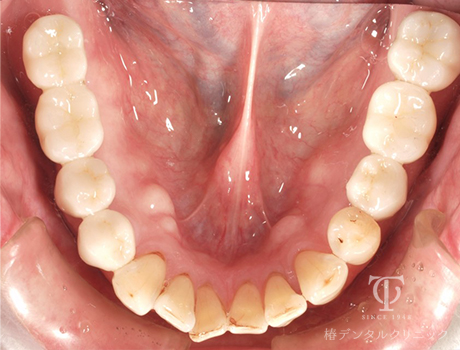

術前

-